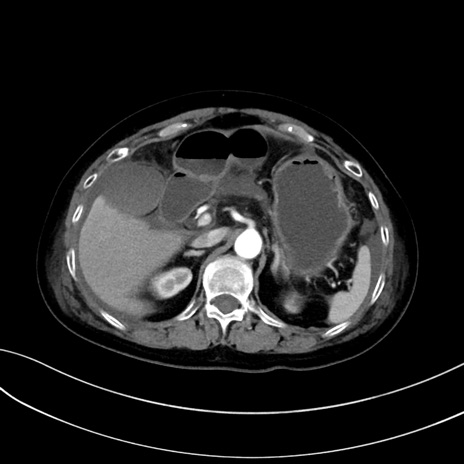

症例13 CT(横断像)1日半後